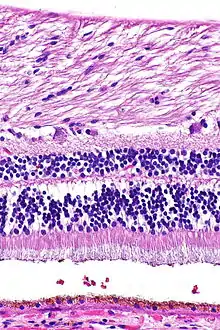

Retina (part of the eye) stained with hematoxylin and eosin, cell nuclei stained blue-purple and extracellular material stained pink.

H&E is the combination of two histological stains: hematoxylin and eosin. The hematoxylin stains cell nuclei a purplish blue, and eosin stains the extracellular matrix and cytoplasm pink, with other structures taking on different shades, hues, and combinations of these colors.[5][6] Hence a pathologist can easily differentiate between the nuclear and cytoplasmic parts of a cell, and additionally, the overall patterns of coloration from the stain show the general layout and distribution of cells and provides a general overview of a tissue sample's structure.[7] Thus, pattern recognition, both by expert humans themselves and by software that aids those experts (in digital pathology), provides histologic information.

Hematoxylin principally colors the nuclei of cells blue or dark-purple,[6][15][14] along with a few other tissues, such as keratohyalin granules and calcified material. Eosin stains the cytoplasm and some other structures including extracellular matrix such as collagen[5][7][14] in up to five shades of pink.[8] The eosinophilic (substances that are stained by eosin)[5] structures are generally composed of intracellular or extracellular proteins. The Lewy bodies and Mallory bodies are examples of eosinophilic structures. Most of the cytoplasm is eosinophilic and is rendered pink.[10][15] Red blood cells are stained intensely red.